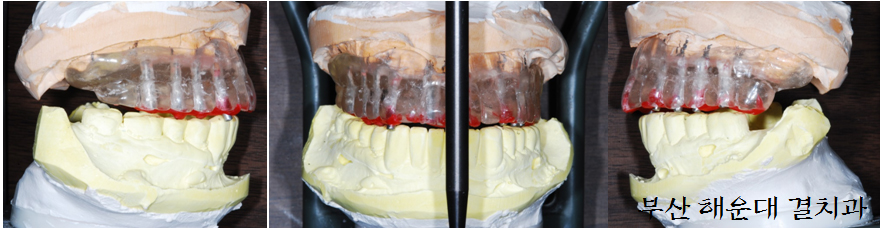

03. 컴퓨터 가상 수술 및 임플란트 수술 유도장치 제작

환자분 귀가 후, 결정된 내용을 기반으로 수술 준비를 시작합니다. 컴퓨터 가상수술을 시행, CT촬영가이드의 방향 및 위치를 수정하여 임플란트 수술유도장치를 제작하고 수술에 필요한 임플란트의 종류, 임플란트 크기와 골이식 재료등을 준비 합니다.

(위 사진은 환자분의 동의 하에 게시하였습니다.)